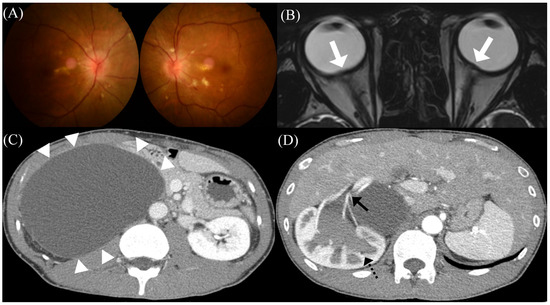

A previously healthy 34-year-old man presented with blurred vision for three weeks. The patient had a three-month preceding history of worsening headache that was moderate to severe in intensity, occurred in the whole cranium, was pulsatile in nature, and was accompanied by nausea/vomiting. He reported that conventional medications for migraine were ineffective. On admission, he was hypertensive (160/90 mmHg); however, heart rate and body temperature were normal. He was underweight with a body mass index of 18.4 kg/m2. Fundus examination revealed papilledema in both eyes (Figure 1A). His best-corrected visual acuity was 20/20 in the left eye and 20/22.5 in the right eye. Pupillary light reflex was normal, and visual field defect was absent. Neurological examination was unremarkable except for mild nuchal rigidity. The results of routine serologic testing, including complete blood count, markers of inflammation (e.g., C-reactive protein, erythrocyte sedimentation rate), electrolytes, and blood chemistry, were all normal. Gadolinium-enhanced brain magnetic resonance (MR) imaging revealed bilateral posterior scleral flattening, suggesting intracranial hypertension (Figure 1B). However, there was no other abnormal brain parenchymal lesion or meningeal enhancement. CSF assay showed a markedly increased opening pressure (30.0 cmH2O) without pleocytosis. In addition, the protein concentration and serum/CSF glucose ratio were all within the normal range.

Although a tentative diagnosis of PTCS was made based on ophthalmological, neuroradiological, and laboratory findings, he had neither any common risk factors for primary PTCS (e.g., obesity, recent weight gain) nor a history of drug exposure/medical illness. Therefore, we performed more extensive work-ups for the secondary cause of PTCS, including hormonal studies, brain MR venography, chest/abdomen computed tomography (CT), autoimmune assessment, and tumor marker detection. Although the patient did not show any abdominal symptoms or signs (e.g., pain, distention), abdomen CT with contrast enhancement revealed a huge benign cystic lesion (14.7 × 10.6 × 16.4 cm) in the right retroperitoneal space, which originated from the mesentery and resulted in hydronephrosis due to external compression of the right kidney (Figure 1C,D). The lesion was pathologically confirmed to be a mesenteric benign cyst. There were neither evidence for mechanical compression nor hormonal abnormalities [e.g., adrenocorticotrophic hormone (ACTH) stimulation test, aldosterone-to-renin ratio] suggestive of adrenal gland involvement. Captopril renal scintigraphy confirmed that his high blood pressure was associated with renovascular hypertension of the right kidney. Other evaluations for the secondary cause of PTCS were unremarkable. Transthoracic echocardiography showed mild left ventricular hypertrophy with a normal ejection fraction of 60.3%, without other chamber or valvular abnormalities. Spirometry demonstrated a normal forced expiratory volume in 1 s/forced vital capacity (FEV1/FVC = 98.1% predicted) with a decreased FVC (73% predicted), which indicated a restrictive pattern.

Figure 1. Initial clinical and radiological presentations of the patient. (A) Initial fundus photography showing bilateral papilledema and visible hard exudates at the posterior pole. (B) T2-weighted brain magnetic resonance images showing the flattening of the posterior sclera bilaterally, suggestive of intracranial hypertension (white arrows). (C) Abdominal computed tomography with contrast enhancement showing a huge benign cystic lesion (white arrowheads), (D) resulting in hydronephrosis (black dotted arrow) and (D) extrinsic compression of the renal artery of the right kidney (black arrow).